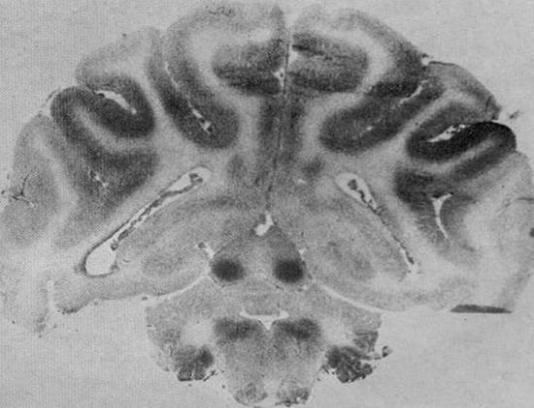

Figure 2:  Autoradiograph showing blood flow in the brain of a newborn monkey.

The greatest blood flow is to the inferior colliculi in the midbrain.  High blood flow is

also seen in other subcortical structures and inner sulci of the cerebral cortex.

From Myers RE. Two patterns of perinatal brain damage and their conditions of

occurrence.  Am J Obstet Gynecol. 1972 Jan 15;112(2):246-76, figure 7, p254.